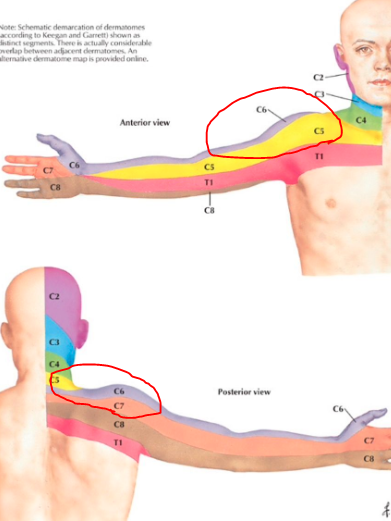

아래 그림을 보자.

경추 신경이 지배하는 영역을 보여주는 그림이다.

해당 신경이 눌리거나 자극이 된다면, 해당 부위를 따라

통증, 저린감, 감각저하 등이 생길 수 있다.

다시 한번 경추 신경의 지배영역을 보자

빨간색으로 표시한 부분이 아파하시는데

C5-6-7 사이에 해당하는 부분이다.

어깨 자체의 문제가 아니라, 목에 의해 생긴 증상일 확률이 매우 높을 것임을 알 수 있다.